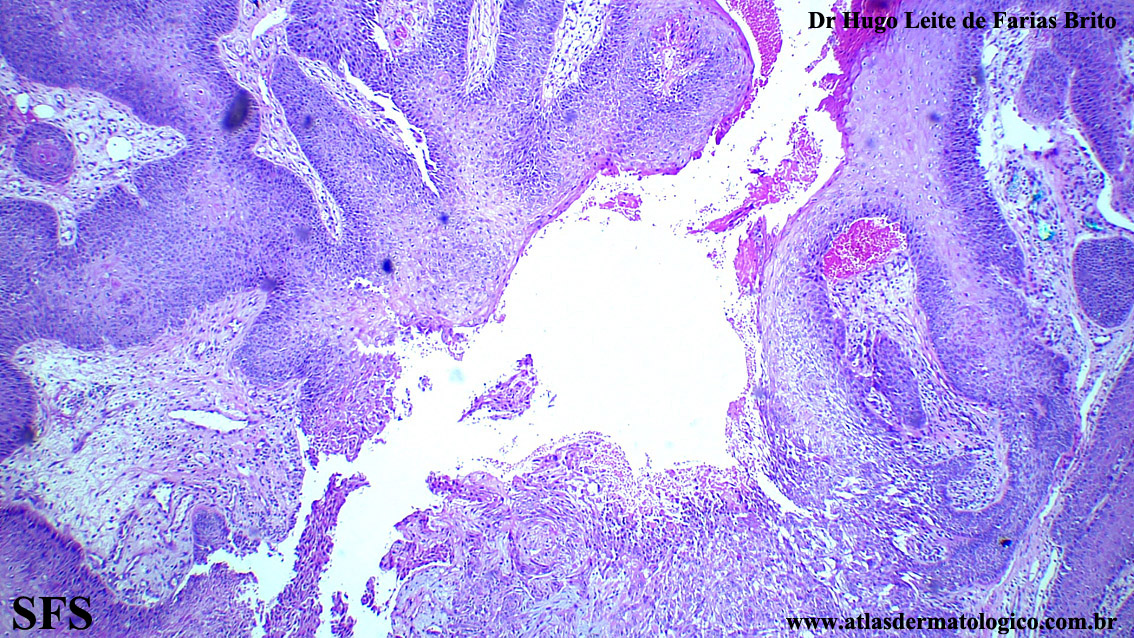

trichilemmoma-desmoplastic_trichilemmoma